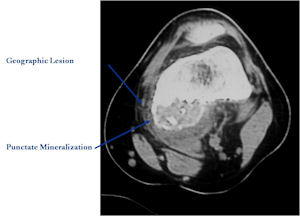

CT Scan:

- More useful for detecting mineralization and evaluating extent of bone destruction than plain X-ray

- The lesion may be entirely radiolucent but usually shows some degree of mineralization. Mineralization may appear stippled like cartilage but do not see chondroid pathologically. Mineralization is sometimes better detected on a CT scan rather than an x-ray.